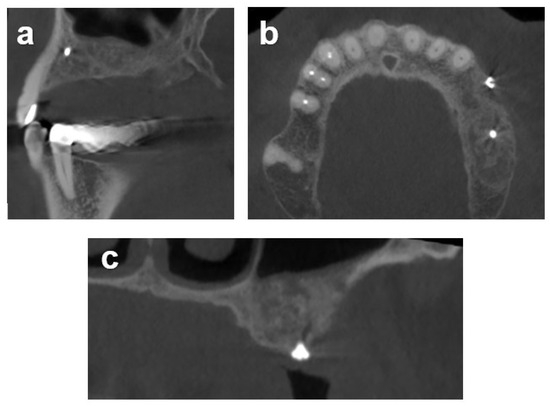

2.7.1. Case 1